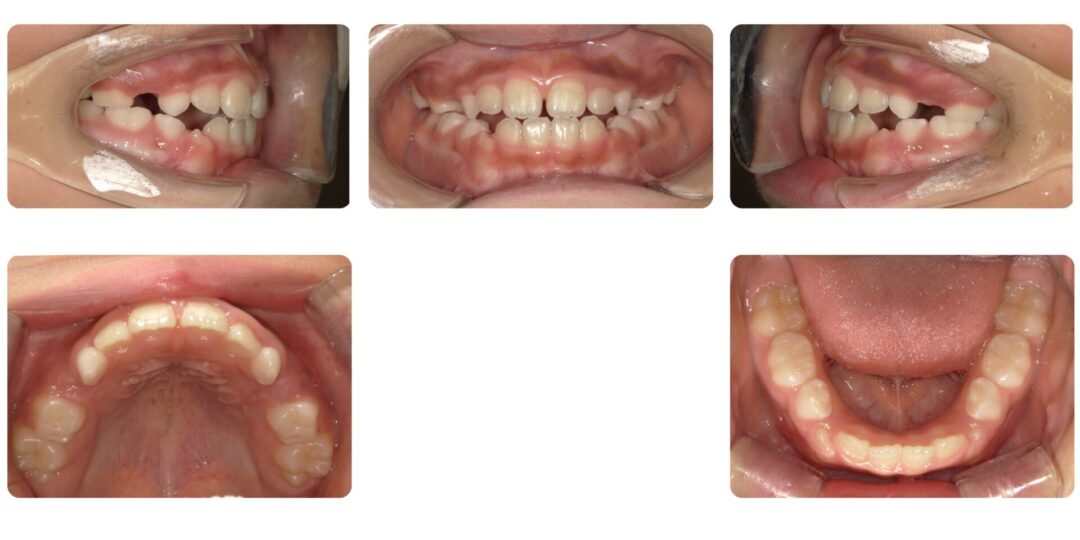

反対咬合を伴う骨格性開咬|初診時7歳

第一期治療 プレオルソによる歯列矯正

1年5ヶ月